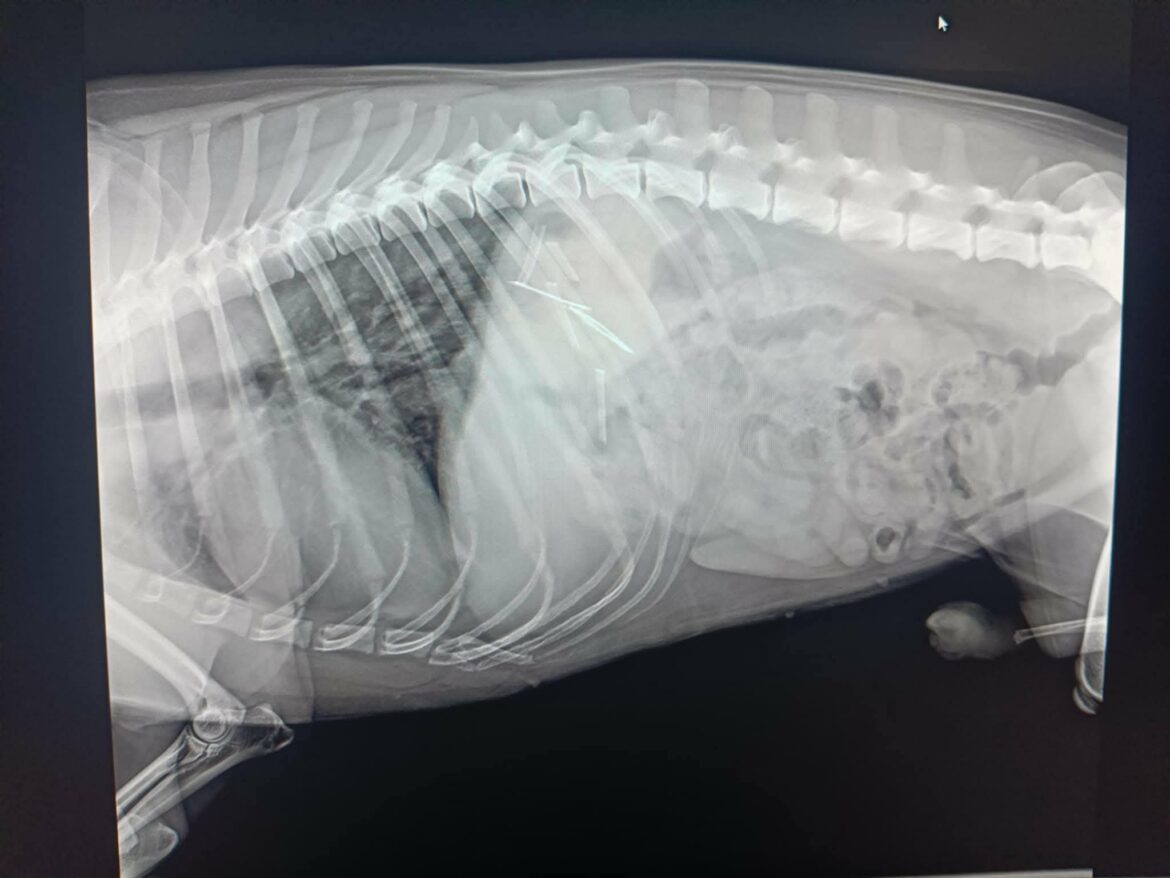

Dalej pisze o tym, jak podczas niedzielnego spaceru zauważyła, że z pyska jej psa wystają… szpilki. Jak się okazało w gabinecie weterynaryjnym, do którego niezwłocznie się udali, miał je również w żołądku. Niezbędna była interwencja chirurga.